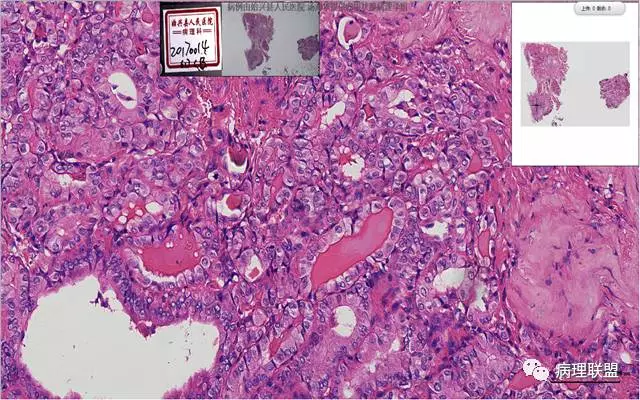

患者,女,45岁,发现双侧甲状腺肿物半月余。大体所见:左侧甲状腺肿物:4.3*5*4cm肿物一个,包膜完整,光滑,质脆,中央见出血。右侧甲状腺组织:3*1.6*1.5cm及1*1*0.8cm组织两块,其中较大的组织切开见内有0.8cm及1.2cm两个,质硬,灰白色,界不清,较小的,切开见灰黄色,质脆。